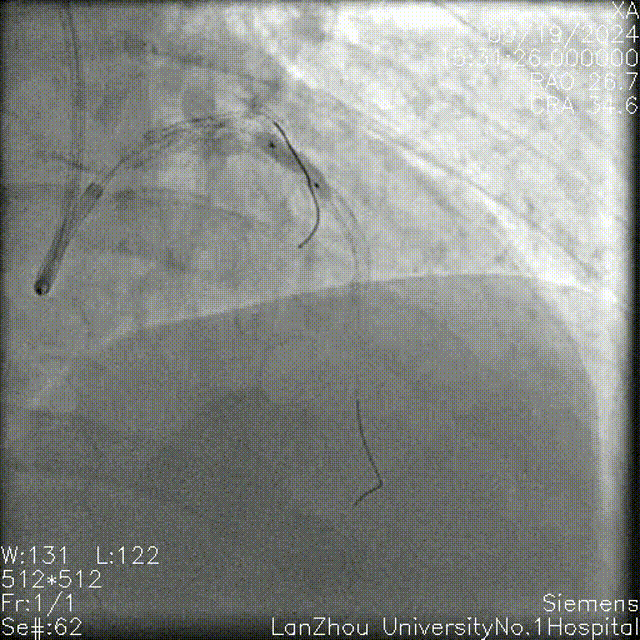

2.75*28mm支架 8atm于前降支近中段释放,复查造影狭窄解除。

复查造影提示回旋支开口仍明显狭窄,考虑使用药球后可能回弹,遂决定行支架植入,于回旋支近端-左主干行Cullotte术,2.75*18mm 10atm释放支架。

前降支Re-wire,1.5mm、2.0 mm、2.5mm球囊扩张回旋支-左主干支架网眼。

与前降支近中段原支架串联前降支近端至左主干 12atm释放3.5*32mm支架。

回旋支Re-wire, 1.5mm、2.0 mm、2.5mm球囊扩张前降支-左主干支架网眼;

2.75*15mm,3.5*12mm球囊扩张前降支-左主干,2.75mm球囊扩张回旋支;

2.75mm,3.5mm 8atm対吻扩张。